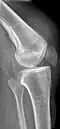

X-ray of a tear of the patellar tendon. On the left: The kneecap is pulled up. On the right: Significant dent in the soft tissue above the kneecap.

-